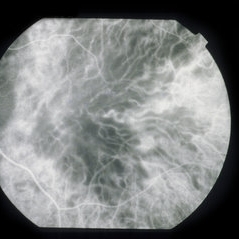

The patient returned on 5/7/93. Vision OU: 20/250. Lesions were beginning to pigment. At this point, ICG was done. The patient has been followed.

The reason I am presenting this case is because of the remarkable ICG findings. Note the tremendous hypofluorescence of the posterior pole of each eye. Is this pigment epithelial edema blocking choroidal fluorescence, or is this marked ischemia of the small vessels (including choriocapillaris) of the choroid?

I have seen two other cases of AMPPE in the acute phase, each of which show this same finding.